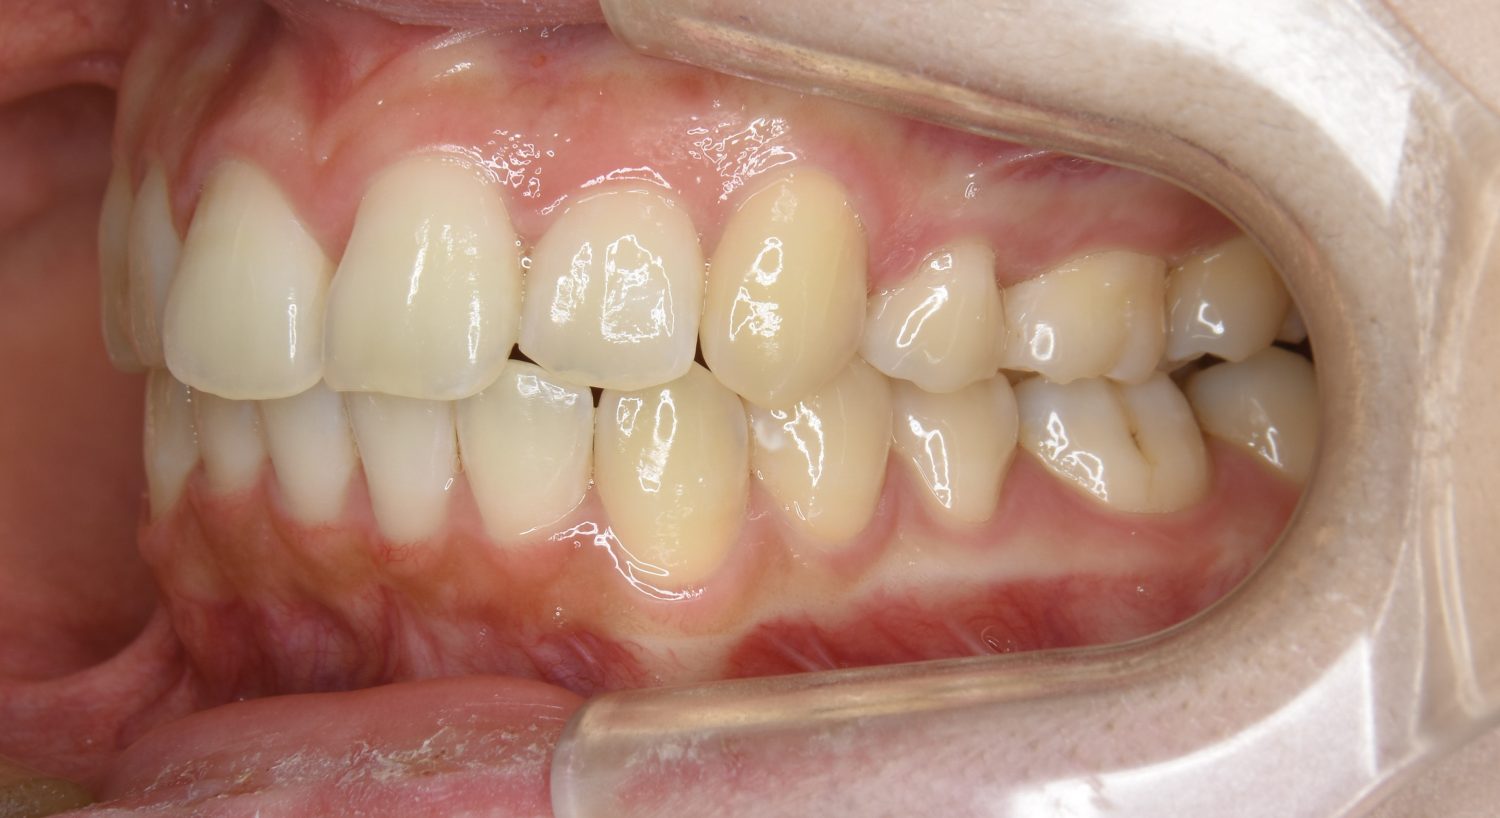

上顎前突の症例紹介②

Before

After

主訴

出っ歯を治したい。

治療内容

上顎両側第一小臼歯を抜歯し、上下ラビアルブラケット(唇側装置)にて治療を行いました。

治療費

1,000,000 円(税込)

治療期間

25ヶ月

通院回数

25回

想定されたリスク

※なし

丸山和宏先生

ピーススマイル矯正歯科

上顎前歯の前突により口元の突出が認められました。上の左右の第一小臼歯を抜歯し上顎前歯を後退させることで口元の突出感は改善し、咬合も良好な状態となりました。